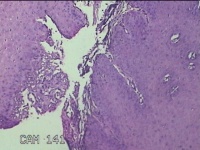

口腔黏膜肿物

性别

男

年龄

6岁

临床诊断

口腔黏膜粘液囊肿

一般病史

右下唇部一月余。

标本名称

大体所见

灰白粉红色囊性肿物0.7x0.5x0.3cm一个,表面光滑。

良性病变。